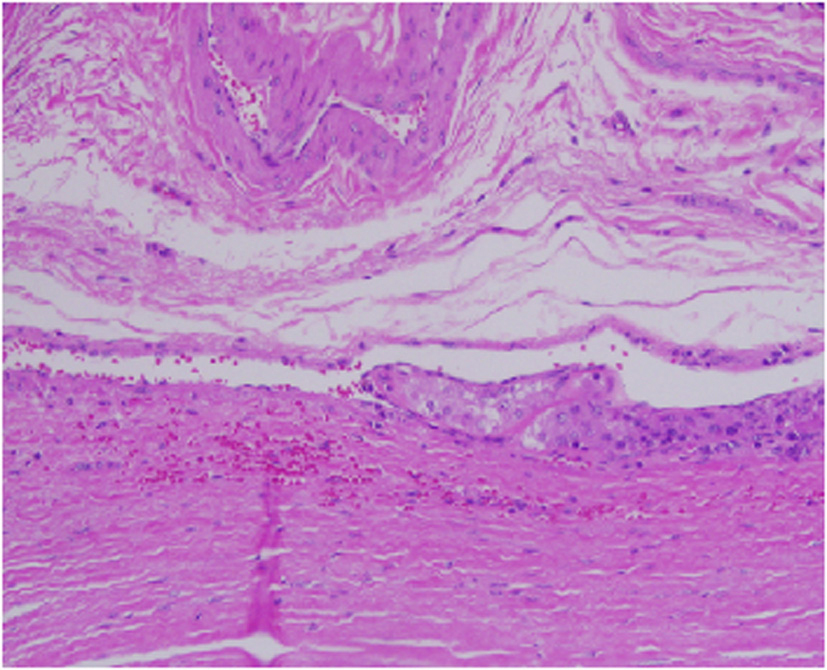

Architecturally, the lesion shows a solid to trabecular growth pattern and is associated with hemorrhage and hemosiderin deposition (Fig. 4). In addition, there are foci highly suspicious for lymph-vascular invasion, and the lesion appears to be poorly encapsulated, with islands of tumor separated by thick fibrous bands (Fig. 5). Morphologically, the cytoplasm is clear to amphophilic, with prominent and distinct cell borders. The background cells have monotonous nuclei with neuroendocrine “salt and pepper” chromatin (Fig. 6). The cells of concern range from moderately pleomorphic to wildly atypical and have irregular nuclear contours. In many areas multinucleation is identified. The nucleoli range from inconspicuous to prominent with cherry-red eosinophilia, irregular membranes and peri-nucleolar halos, the latter being a feature almost exclusively seen in PCA [12] (Fig. 7). The sum total of these findings supports a diagnosis of intrathyroidal parathyroid carcinoma (Fig. 8, 9). In this case, the hypercellular parathyroid tissue noted in several of the sections is morphologically distinct from the predominant neoplasm, interpreted as carcinoma (Fig. 9).

![]() Click for large image | Figure 5. This focus is highly suspicious for invasion of an adjacent vessel by parathyroid carcinoma. |